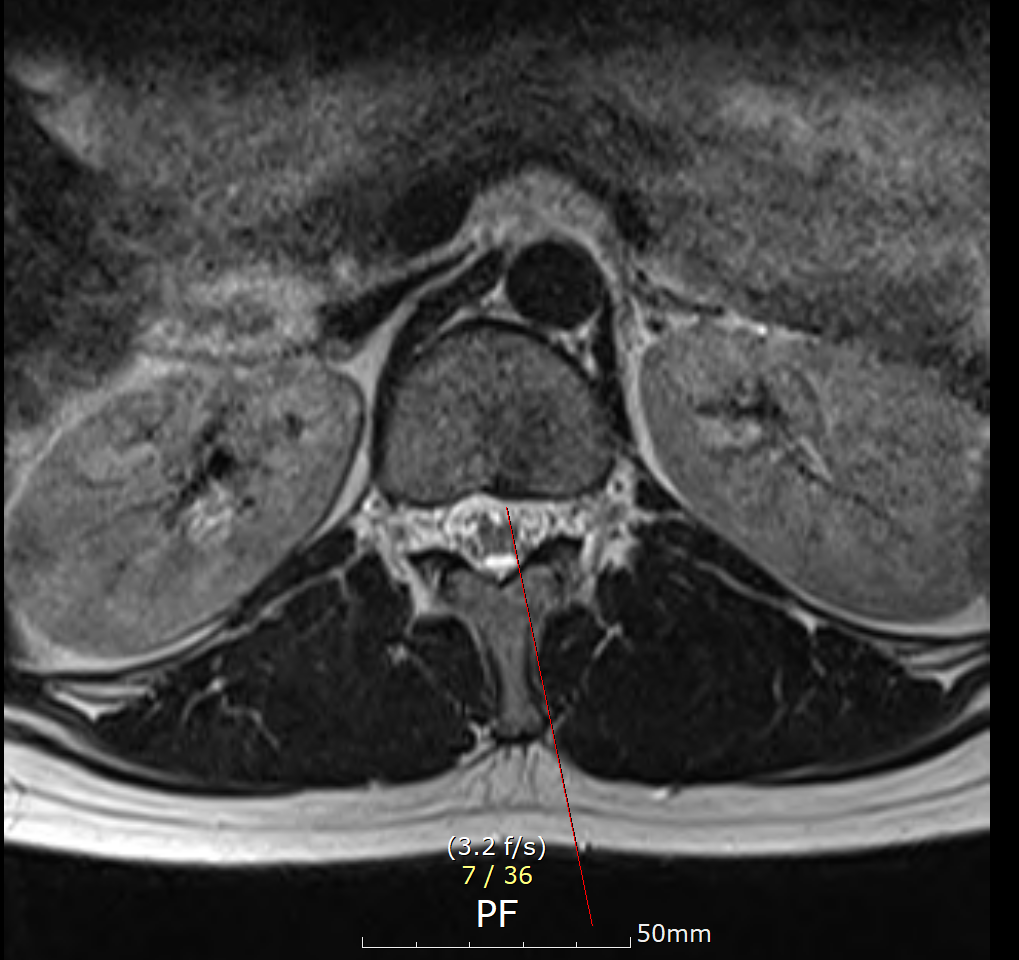

T12-L1 level에서 disc가 뒤쪽 Lt. central aspect로 protrusion되어 있고 mild한 dural sac indentation을 주고 있음.

아래 사진에 있는 부위가 아마 T12/L1 사이에 디스크가 살짝 뒤로 빠져있다는 부위이실겁니다.

옆에서 보면 두번째 사진이구요.

우선은 이 디스크 내장증으로 인한 연관통으로 보고 요추전만 자세를 잘 실천해보시는게 가장 우선 필요한 조치이겠습니다.

수술을 주로 다루는 신경외과, 정형외과 선생님들의 경우에 심한 디스크탈출 및 신경뿌리를 누르는 신경뿌리병증이 생길만한 병변만 통증을 유발한다고 보시기 때문에 문제될만한 병변이 없다고 이야기 하셨을텐데 저렇게 작게 찢어진 디스크 때문에도 충분히 통증이 생길 수 있습니다. 물론 찢어진 디스크의 위치에 비해 통증이 밑에 있는 편이시지만 이게 불가능한건 아닙니다. 디스크 내장증이라고 하며 이럴때는 요추전만 자세가 가장 중요합니다.